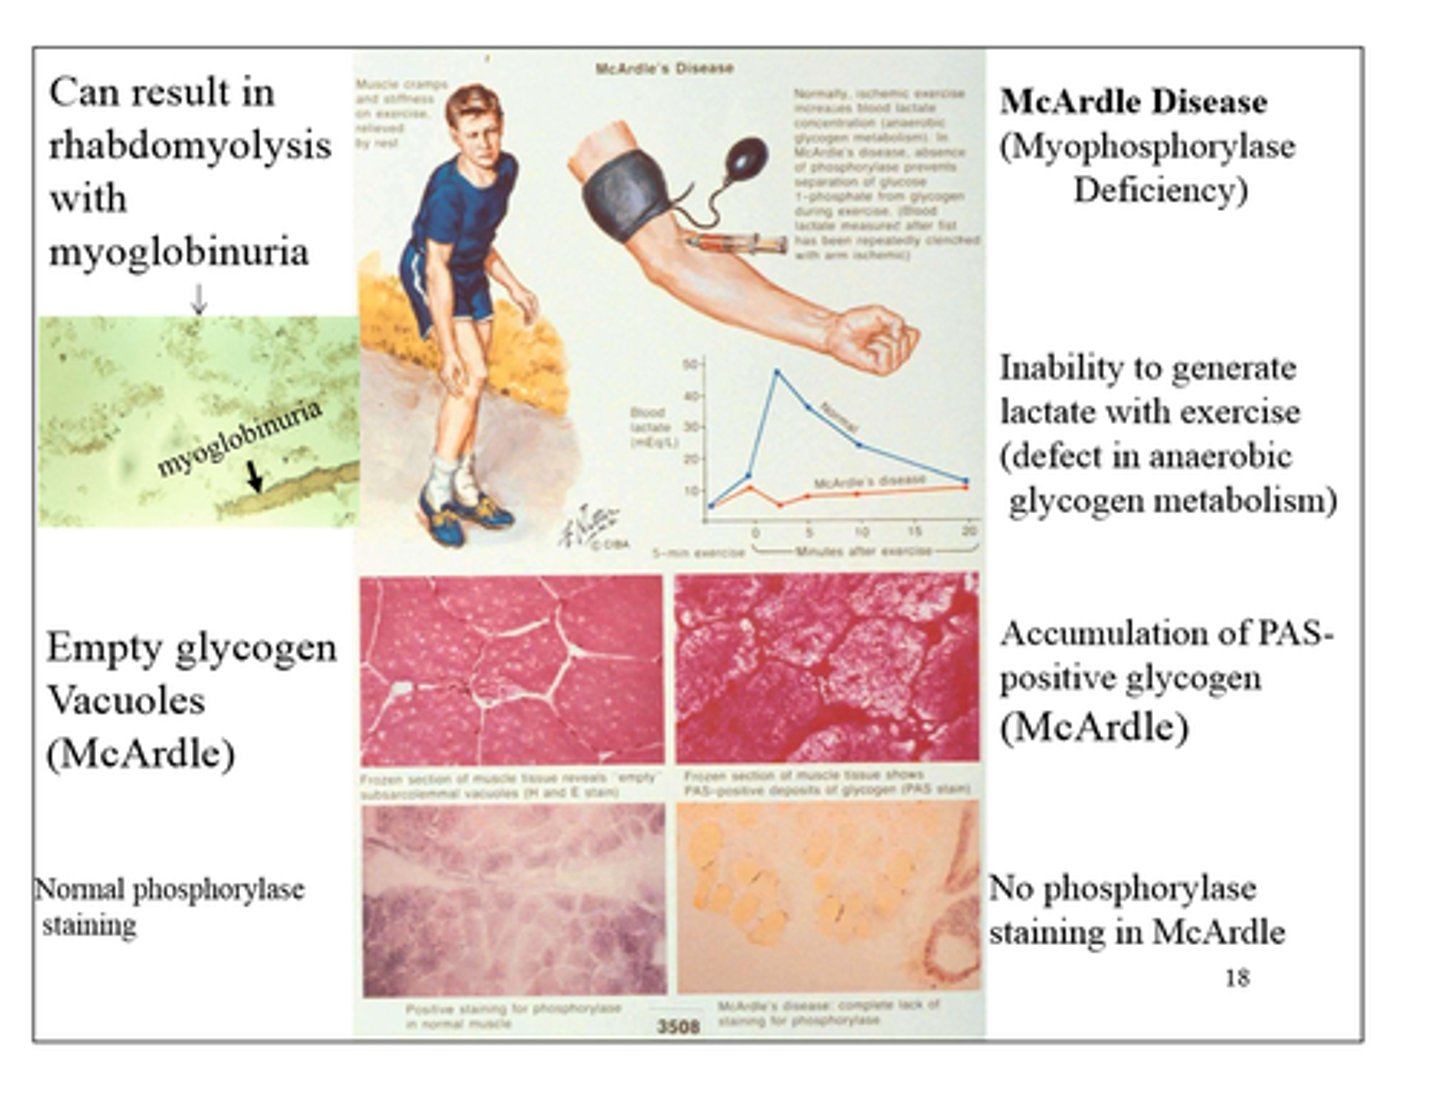

Chronic exercise intolerance with myalgia, painful cramps, myoglobinuria, arrythemia

AR McArdle disease

(skeletal muscle glycogen phosphorylase deficiency)

-defect in anaerobic glycogen metabolism